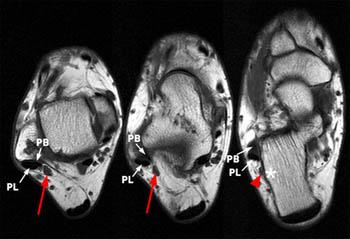

Thigh muscles also protect neurovascular structures as they go through the proximal hip joint to the knee and lower leg (3). Accessory Muscles of the Ankle - Radsource